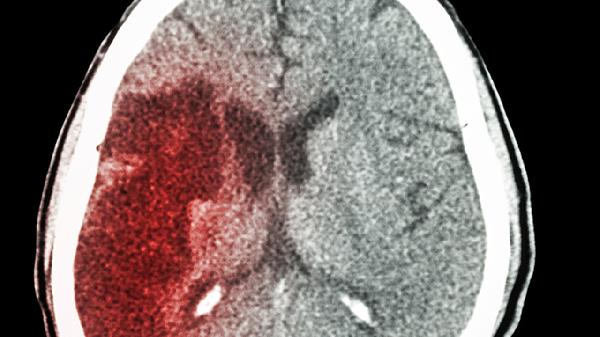

5、脑血管病预防人群

对存在高血压、糖尿病等脑血管病危险因素者,可遵医嘱作为二级预防用药。禁用于急性脑出血期或严重凝血功能障碍患者,用药前需评估出血风险。